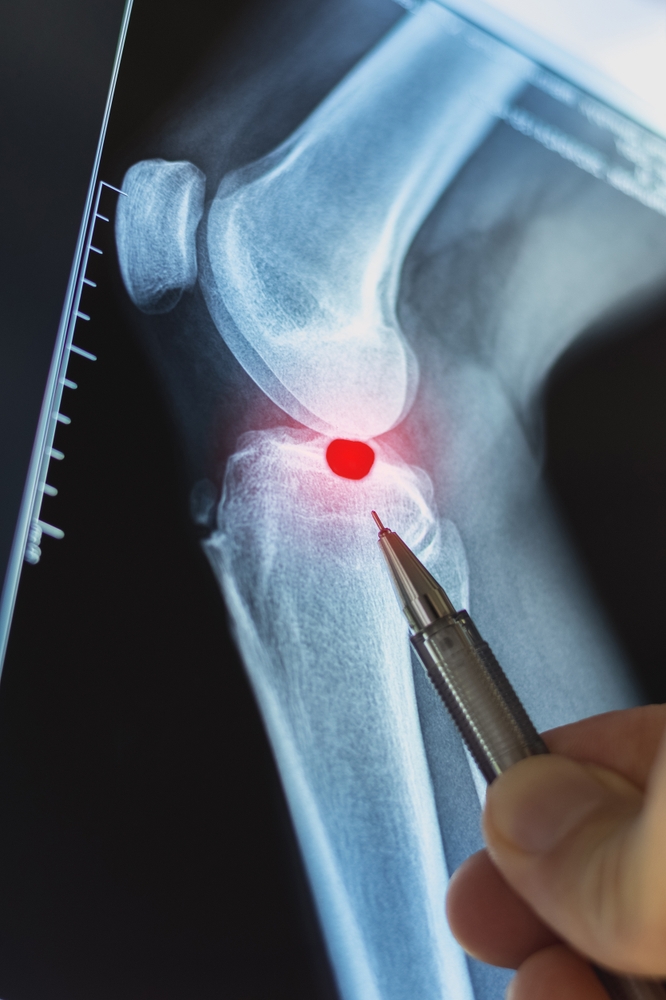

• Osteofitai – ilgainiui sąnariuose ar jų prieigose susiformuojančios ataugos, žinomos kaip kaulinės išaugos ar „kaulo spurga“.

• Judesio apribojimas arba skausmas judant – dažniausiai, kai ataugos formuojasi prie sąnarių (klubo, kelio, čiurnos, pirštų).

Nustačius įtartiną kaulinį iškilimą, gydytojas pirmiausia atliks apžiūrą ir išklausinės apie patiriamus pojūčius. Diagnozę patvirtinti dažniausiai padeda vaizdiniai tyrimai:

• Rentgenogramos;

• Kompiuterinė tomografija (KT);

• Magnetinio rezonanso tomografija (MRT).